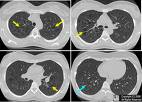

(7)肺 LCH的肺部病變可做為全身病變的一部分,也可能單獨存在,即所謂原發性肺LCH。任何年齡都可出現肺部病變,但兒童期多見於嬰兒,表現為輕重不等的呼吸困難,缺氧和肺的順應性變化。重者可出現氣胸、皮下氣腫,極易發生呼吸衰竭而死亡。肺功能檢查常表現限制性損害。

(5)X線檢查 肺部X線檢查多為肺紋理呈網狀或網點狀陰影,顆粒邊緣模糊,不按氣管分支排列。有的肺野呈毛玻璃狀,但多數病例肺透光度增加,常見小囊狀氣腫,重者呈峰窩肺樣。可伴間質氣腫、縱隔氣腫、皮下氣腫或氣胸,不少患者可合併肺炎,此時更易發生肺囊性改變,肺炎消退後,囊性變可消失,但網粒狀改變更為明顯,久病者可出現肺纖維化。骨骼X線改變見前述。